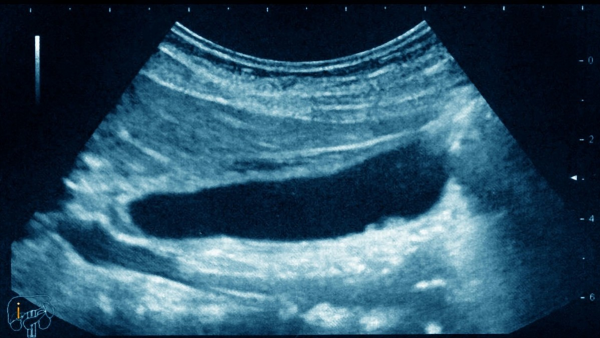

三、檢查膽囊異常,選用B超即可

B超是檢查膽囊疾病的主要方式,可以比較準確的診斷出膽石症以及炎症的發生。因此來說,不管是急性還是慢性的膽囊炎,都可以採用B超的方式進行檢查。若是懷疑有膽管結石的情況,也可以做MRCP 或者 ERCP 輔助檢查。

對於慢性的膽囊炎患者而言,透過B超可以發現膽囊壁增厚、出現暗帶、囊腔內出現回聲、膽囊萎縮和結石等情況。而急性的膽囊炎患者做B超的話,可能會在影像中顯示出腫大的膽囊、膽囊壁水腫增厚以及結石等現象。

B超是較為普通的體檢方式,價格也相對便宜。所以說,若發現身體異常的話,最好去醫院檢查一下,尤其是一些家族中患有膽囊結石、膽囊炎病史的人群,需要特別注意。